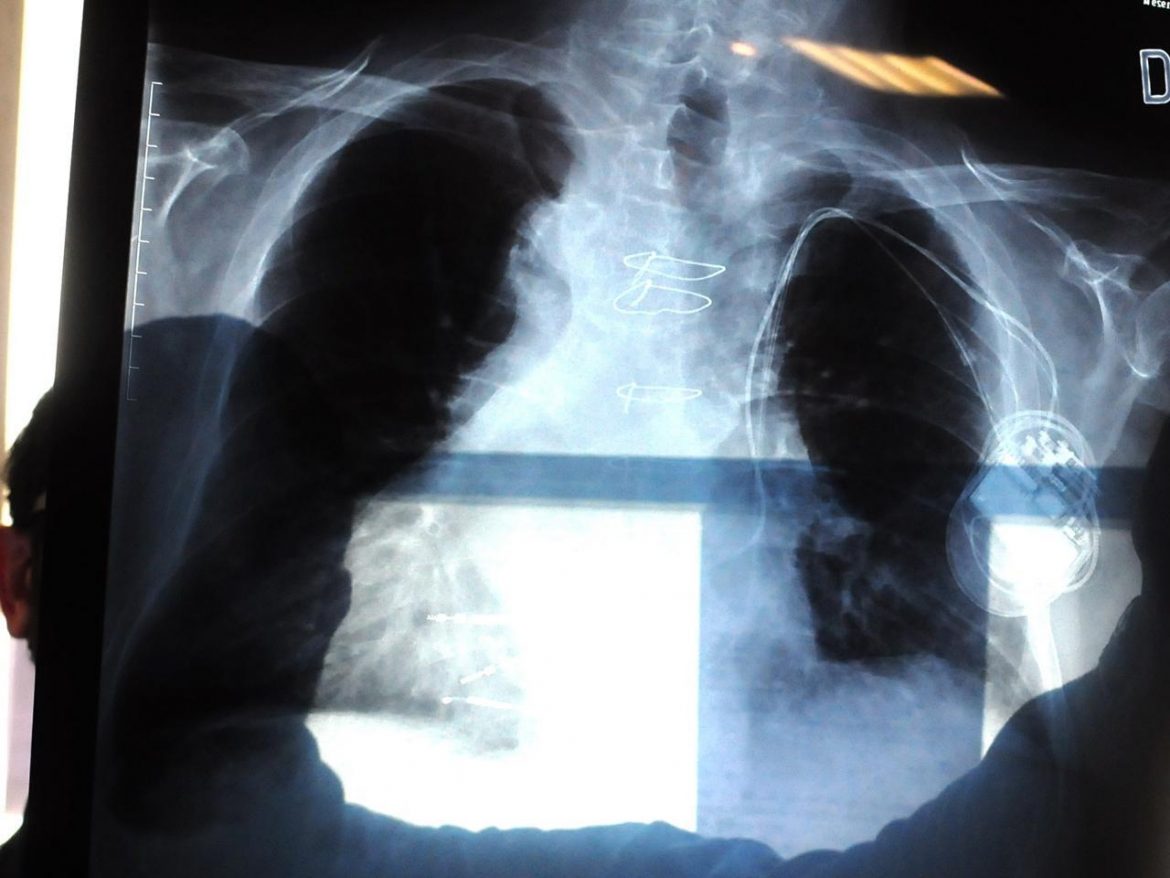

Roma, 7 mag. (Adnkronos Salute) – In Italia ogni anno si registrano circa 41mila nuove diagnosi di tumore polmonare. Negli ultimi anni l’immunoterapia ha però rivoluzionato il trattamento dei tumori, raggiungendo sorprendenti risultati clinici, anche nelle neoplasie polmonari. La buona notizia è che una discreta percentuale di tutti i soggetti con tumore al polmone, che in precedenza avevano una prognosi infausta, rispondono all’immunoterapia con inibitori di PD-1/PD-L1 e diventano lungo sopravviventi. Purtroppo, però, una parte non trascurabile di pazienti non beneficia di tale trattamento. Un recente studio (https://www.sciencedirect.com/science/article/pii/S0923753420421702) del team guidato da Marcello Maugeri-Saccà, oncologo medico e ricercatore presso la Divisione di Oncologia medica 2 dell’Irccs Istituto nazionale tumori Regina Elena di Roma, pubblicato su ‘Annals of Oncology’ (rivista ufficiale dell’European Society for Medical Oncology), rivela che un sottogruppo di pazienti con adenocarcinomi polmonari che presentano mutazioni contemporanee nei geni KEAP1, PBRM1, SMARCA4 e STK11 è particolarmente svantaggiato e resistente alla immunoterapia. “Da alcuni anni – afferma Maugeri-Saccà in un’intervista pubblicata su Alleati per la Salute (www.alleatiperlasalute.it), il nuovo portale dedicato all’informazione medico-scientifica realizzato da Novartis – per la cura di tali tumori abbiamo a disposizione una nuova e importante arma terapeutica, ovvero l’immunoterapia. Si tratta dei cosiddetti anticorpi monoclonali che hanno l’obiettivo di stimolare il nostro sistema immunitario contro la malattia”. Nonostante gli ottimi risultati in termini di efficacia clinica, purtroppo non tutti i pazienti traggono giovamento da questo trattamento. “Il nostro studio – prosegue l’oncologo – ha identificato un sottogruppo di pazienti che non hanno beneficio con l’immunoterapia, da ricondursi alla presenza nel tumore di uno specifico repertorio mutazionale. Questo si traduce in una progressione di malattia più rapida e in una minore sopravvivenza rispetto ai pazienti che non presentano specifiche mutazioni. Stiamo parlando del 10-15% di tutti i soggetti con adenocarcinoma polmonare, la neoplasia polmonare più frequente”.”Si tratta di mutazioni coesistenti – spiega Maugeri-Saccà – che coinvolgono almeno due dei seguenti geni: KEAP1, PBRM1, SMARCA4 e STK11. Tale assetto mutazionale identifica dei tumori immunologicamente ‘freddi’, nonostante un carico mutazionale elevato, come descritto nello studio. Anche se relativamente poco noti, questi geni sono frequentemente mutati nell’adenocarcinoma polmonare. Grazie ai progressi della biologia molecolare e della medicina di precisione nel campo oncologico, attualmente possiamo identificare queste mutazioni in due modi: direttamente sul campione di tessuto tumorale prelevato dal paziente, per esempio su un campione bioptico o intervento chirurgico, oppure possono essere identificate nel Dna tumorale circolante presente nel sangue del paziente, ovvero con un semplice prelievo ematico”. L’identificazione a priori dei pazienti cosiddetti non-rispondenti, secondo l’esperto, può permettere da un lato di evitare di sottoporli inutilmente a una terapia per loro inefficace e con effetti collaterali talvolta pericolosi, dall’altro di studiare i meccanismi di resistenza nel tentativo di sviluppare nuovi approcci farmacologici. “Conoscere l’assetto mutazionale dei tumori prima di iniziare i trattamenti oncologici – sottolinea Maugeri-Saccà – è fondamentale: ci permette di sapere se il tumore è sensibile a un farmaco piuttosto che a un altro, ci fornisce informazioni sulla biologia del tumore e sull’andamento clinico atteso. I risultati del nostro studio ci suggeriscono che conoscere i pazienti i cui tumori presentano queste mutazioni prima di iniziare il trattamento immunoterapico potrebbe rappresentare un ‘campanello d’allarme’ sull’andamento della malattia, che si caratterizza per un andamento più tumultuoso e un basso tasso di risposte all’immunoterapia. D’altra parte, i pazienti che nel tumore non mostrano queste mutazioni sembrano quelli che più di altri beneficiano del trattamento immunoterapico, e che quindi ottengono un prolungato controllo di malattia grazie a questa classe di farmaci.Sebbene si tratti di una scoperta ritenuta “rivoluzionaria”, al momento l’identificazione a priori dei soggetti non-rispondenti non è pratica clinica. “Queste analisi genomiche – conferma Maugeri-Saccà – necessitano di strumentazioni tecniche e di capitale umano che non tutti i centri italiani hanno a disposizione. Si tratta di utilizzare dei pannelli multigenici, se non di sequenziare l’intero esoma (il Dna codificante), mediante next-generation sequencing, al fine di testare contemporaneamente un gran numero di mutazioni”. In tale contesto, “è doveroso sottolineare come questo tipo di scoperte sia frutto di un mix di fattori – conclude l’oncologo – Due su tutti: la collaborazione con altri enti, in questo caso l’Università degli Studi di Roma ‘La Sapienza’, e la multidisciplinarità del gruppo di ricerca (oncologi medici, ricercatori, bioinformatici, patologi). A tal proposito, gli Irccs oncologici sicuramente stanno dando un contributo fondamentale, nel contesto di un programma di collaborazione (Alleanza contro il cancro, Acc) che ha, tra i vari obiettivi, quello di rendere disponibili e riproducibili tecniche di sequenziamento, su scala relativamente ampia, da applicare alla pratica clinica”.Leggi la news anche su: